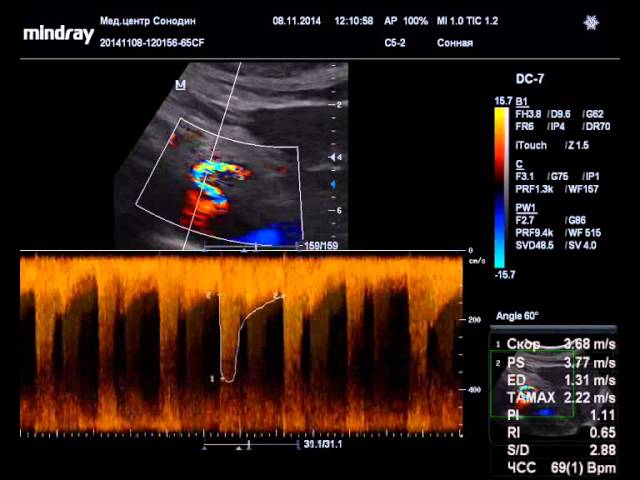

- Ультразвуковая допплерография. На основе ее результатов специалист анализирует скорость кровотока в сосудах и состояние артериального русла.

| Диагностика | Комплексный подход, включающий сбор анамнеза, физикальное обследование и инструментальные методы. | Инструментальные: УЗИ брюшной полости с допплерографией (позволяет оценить кровоток), КТ-ангиография, МРТ-ангиография (наиболее информативны для визуализации стеноза и компрессии), ангиография (инвазивный метод, используется реже). |